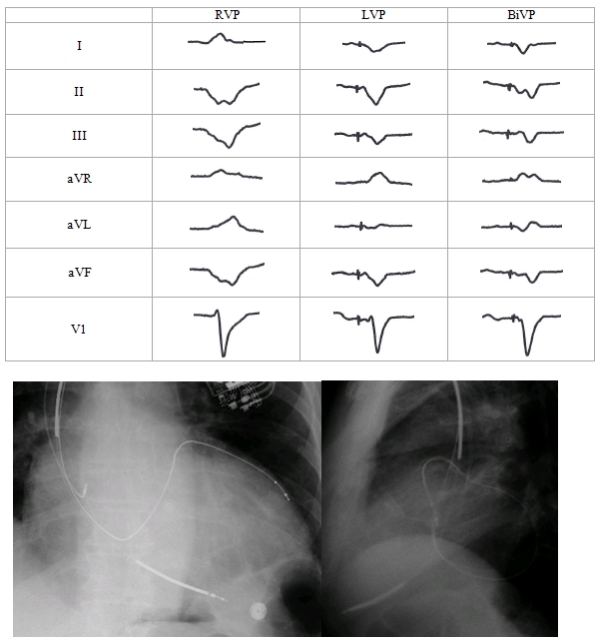

Anodal Stimulation: An Underrecognized Cause of Nonresponders to Cardiac Resynchronization Therapy

Khalin F Dendy, MD, Brian D Powell, MD, […], and Samuel J Asirvatham, MD. Indian Pacing Electrophysiol J. 2011 May-Jun; 11(3): 64–72.